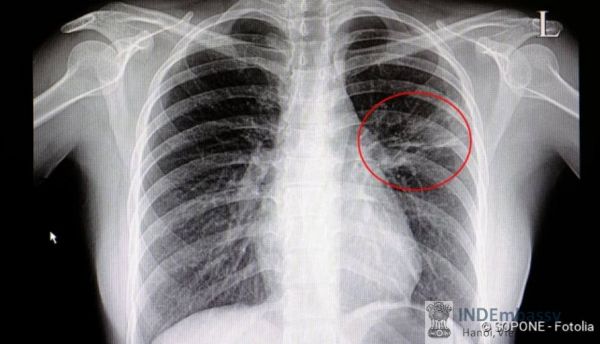

Viêm phổi là một bệnh nhiễm trùng phổi do vi khuẩn, virus, nấm, hoặc ký sinh trùng. Nó được đặc trưng chủ yếu của viêm phế nang trong phổi hoặc phế nang chứa đầy dịch. Một tình trạng rất nghiêm trọng, viêm phổi có thể làm cho một người bị bệnh nặng hoặc thậm chí gây tử vong. Mặc dù bệnh có thể xảy ra ở những người trẻ và khỏe mạnh, nó nguy hiểm nhất đối với người lớn tuổi, trẻ sơ sinh, và những người có bệnh khác hoặc hệ thống miễn dịch bị suy giảm. Tại Hoa Kỳ, hơn 3 triệu người phát triển bệnh viêm phổi mỗi năm, và khoảng 17% được điều trị tại bệnh viện. Hầu hết những người bị viêm phổi hồi phục, nhưng khoảng 5% sẽ thất bại trước tình trạng này.

Vi khuẩn và virus là nguyên nhân chính của bệnh viêm phổi. Khi một người hít phải vi trùng viêm phổi vào phổi và hệ thống miễn dịch của cơ thể không thể không ngăn ngừa, các sinh vật định cư trong các túi khí nhỏ gọi là phế nang và tiếp tục nhân nên. Khi cơ thể gửi các tế bào bạch cầu tấn công các vi trùng, các túi tiết chất lỏng và có mủ - Gây viêm phổi có vi khuẩn, virus, nấm, và nguyên nhân chính khác.